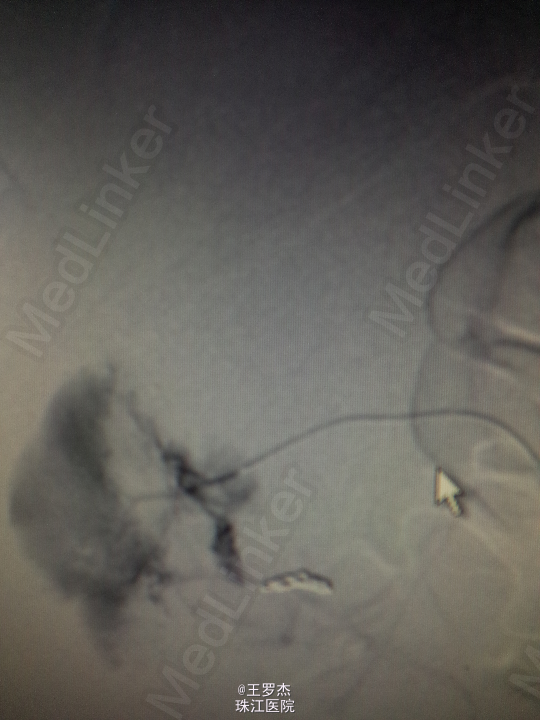

诊断治疗:右肾挫裂伤,保守治疗。3天后复查Hb89g/L,RBC2.65;复查CT提示包膜下及盆腔积血较前增多。请介入科会诊,行右肾动脉选择性栓塞。 介入:右肾挫裂伤,并上极动脉破裂出血及远端多处动静脉瘘形成,成功行超选择性病变血管栓塞术。